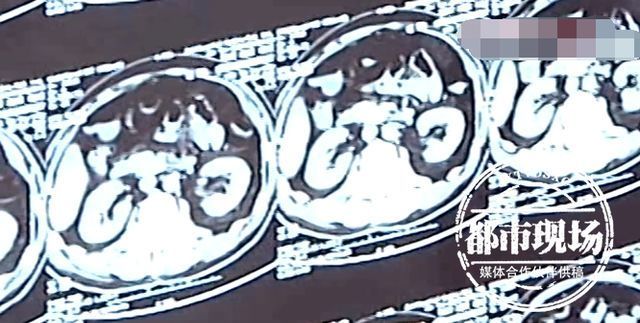

哈尔滨市儿童医院 外科 主任医师 王文生:考虑孩子的情况像肠穿孔,通过我们术前的准备,1月18日晚上给他做了手术。

张鹏是吃了磁力珠四天后才被送到医院救治的,耽误了最佳取出磁力珠的时间,导致肠穿孔,目前只能通过手术治疗。

哈尔滨市儿童医院 外科 主任医师 王文生:这种磁力球我们接触了很多,现在全国也基本达成一个共识,这种磁力球尤其是两个以上的一定要早期去手术治疗或者是胃镜取出来,因为大部分我们发现了都是出现肠穿孔,甚至是出现感染性休克的一个状态。